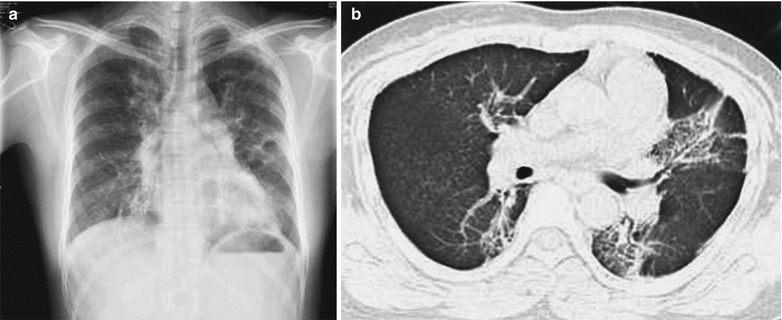

Based on type II, type III is characterized by small patches and flakes of blurry shadows along with bilateral pulmonary markings, which are especially obvious at the middle and medial parts of both lower lungs. The lesions are infiltrative with a size of 1–3 cm (Figs. 23.4, 23.5, 23.6, 23.7, and 23.8).

Fig. 23.6.

Adult measles pneumonia. (a) X-ray demonstrates scattering flakes of ground-glass opacity at both lungs. (b) Reexamination after treatment for 3 days, CT scanning demonstrates multiple ground-glass opacity at both lungs, with paving stone-like lesions

CT Scanning

CT scanning demonstrates pulmonary consolidation, thickened bronchial vascular bundles, ground-glass opacity, lesions at the lobular center, and nodular shadows (Figs. 23.18 and 23.19). In rare cases, cords like shadow can be demonstrated, with accompanying pleural effusion.